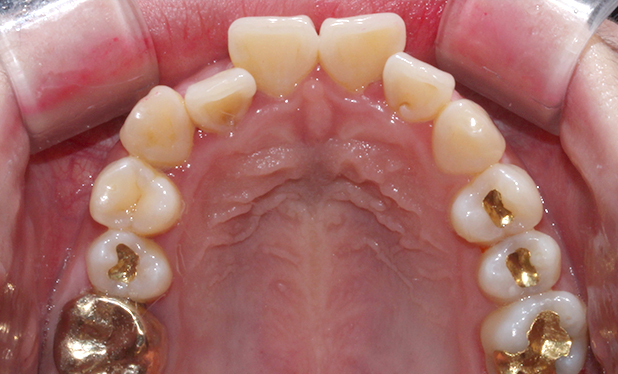

상악 오른쪽 측절치,

사진상으로 왼쪽이

반대로 물리는 반대교합입니다.

간단히 말해 덧니인데

옆에 송곳니와 앞니로 인해

더 도드라져 보이는 상태였습니다.

필요한 공간도 크게 부족하지

않기 때문에 2D교정으로

진행하기로 하였습니다.

[치료계획]

상악 2D교정,

치아모양 수정,

IPR (치아사이공간 삭제)